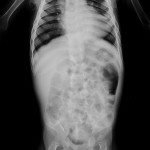

INFANTILE OSTEOPOROSIS

Infant investigated for severe anemia